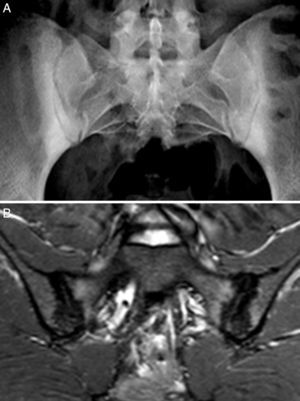

Caso 2: mujer de 28 años, con dolor lumbar crónico de características inflamatorias y dolor generalizado con criterios de FM, de un año de evolución. El HLA B27 fue negativo y los ANA positivos a título bajo 1/80 sin especificidad. La radiografía simple mostró esclerosis de ambas sacroiliacas con un diagnóstico diferencial difícil entre osteítis condensante del iliaco y sacroilitis. La RM mostró esclerosis, erosiones y edema óseo demostrativo de sacroilitis (fig. 2). La paciente reunía, por lo tanto, criterios ASAS de espondiloartritis axial. Además, presentaba un cuadro digestivo asociado con dispepsia, náuseas y vómitos. La serología de cribado de EC fue negativa. La tipificación HLA mostró DQ7 y DQ6, con ausencia de DQ2 y de DQ8. La biopsia duodenal mostró un infiltrado intraepitelial de 44 linfocitos CD3 por 100 enterocitos, sin atrofia de vellosidades. El cuadro clínico remitió tras 7 meses de DSG, tanto el dolor lumbar como el dolor generalizado, y el cuadro digestivo. A los 20 meses de seguimiento, se mantenía la remisión clínica y refería recidiva de dolor y digestiva cuando había tomado gluten.